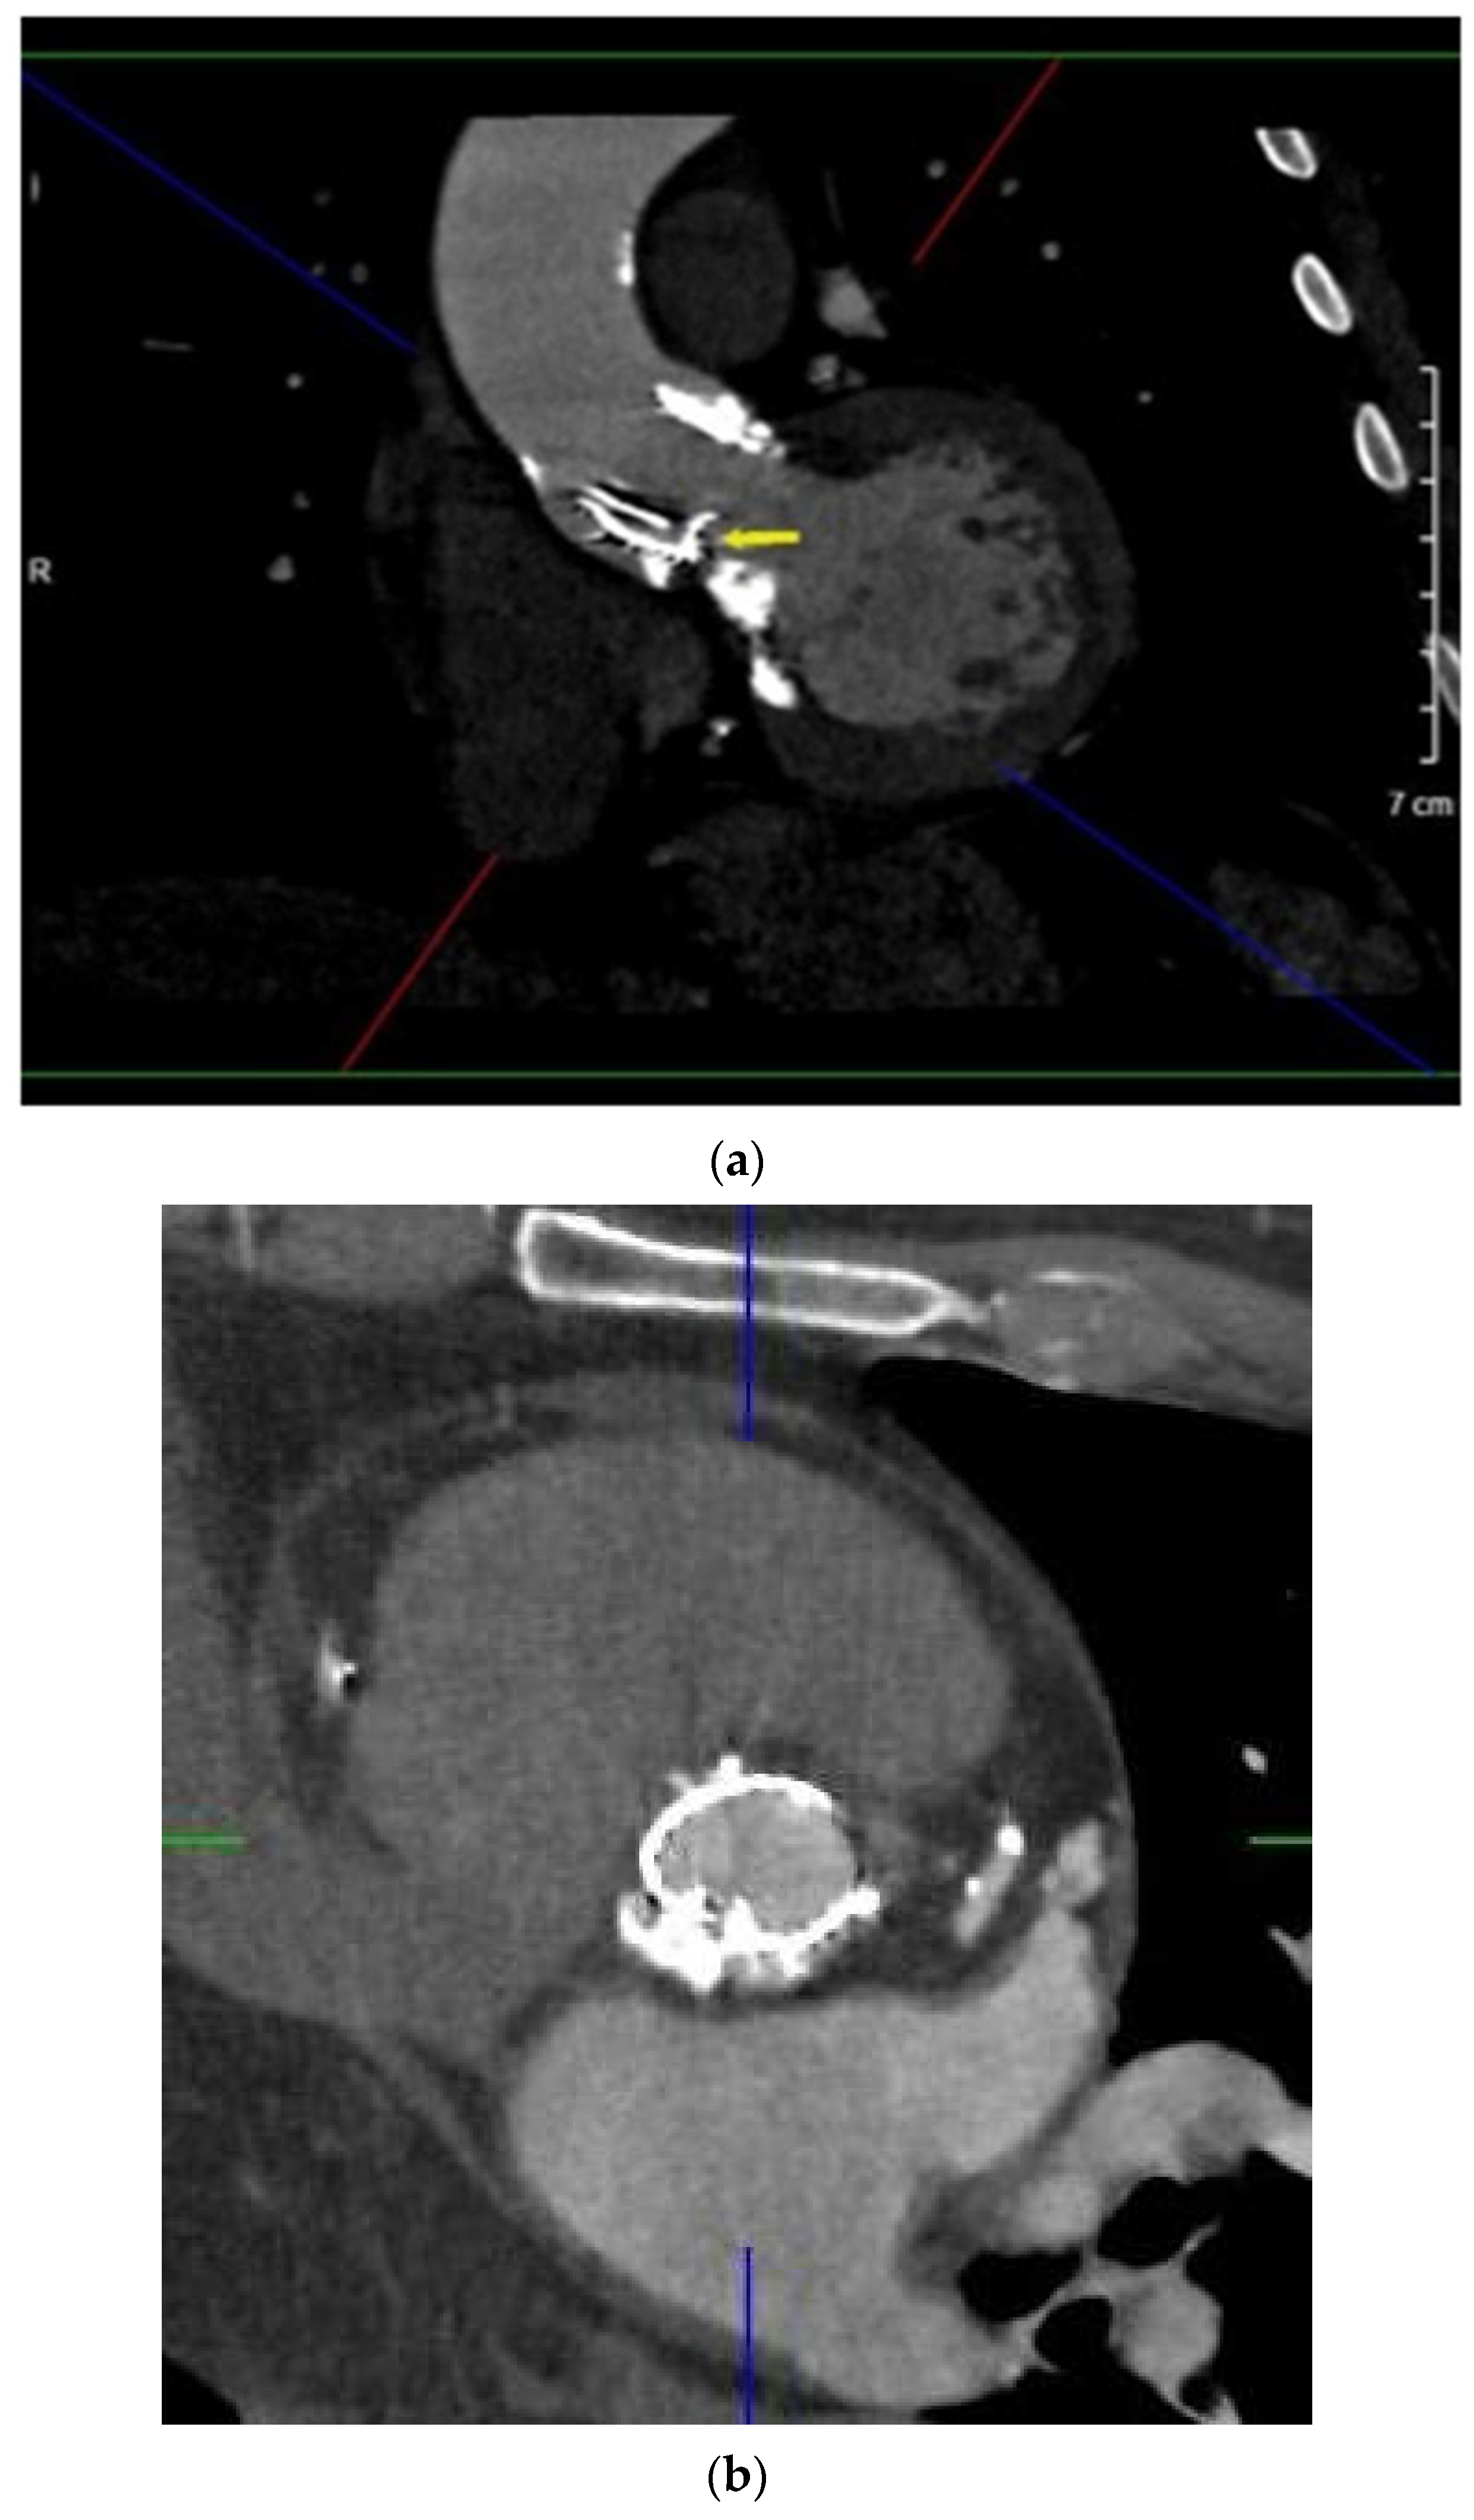

2.1. Case 1

2.2. Case 2